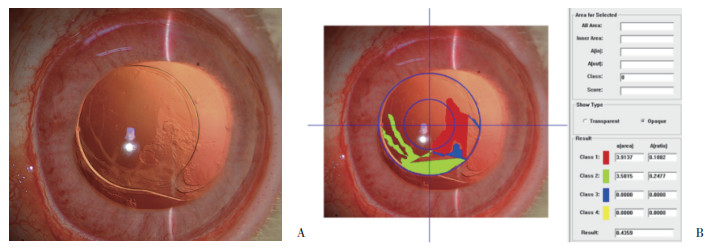

A组于术后14 d开始出现后囊膜混浊,见图 1、图 2。B组于术后7 d开始出现后囊膜混浊,见图 3。随着时间延长,2组后囊膜混浊程度逐渐加重。术后7 d、14 d、28 d A组平均后囊膜混浊评分小于B组,差异有统计学意义(P < 0.05),见表 2。

| 图 3 B组术后28 d裂隙灯检查晶状体后囊膜图像(A)及对应PCO-CAAS图像定量分析系统后囊膜混浊评分(B) × 16 Fig.3 Posterior capsular image (A) observed by slit lamp inspection and corresponding posterior capsular opacity score measured by PCO-CAAS (B) in group B at 28 days after surgery × 16 |

囊膜生物相容性是指残留于晶状体囊膜的晶状体上皮细胞对IOL的创面愈合反应,常用后囊膜混浊程度作为评价指标[1]。本研究中,A组IOL后表面经紫外线/臭氧处理,增加了其黏附性[13],与后囊膜贴合紧密,可使已居于中间的晶状体上皮细胞因缺少营养和机械性压迫而死亡,亦阻碍了晶状体上皮细胞从赤道部向后囊膜中央区迁移,故后囊膜混浊出现时间晚、程度轻,囊膜生物相容性较好。B组后囊膜混浊出现时间早,程度重,与LEE等[14]的研究结果一致。XU等[15]发现固定于IOL表面的亲水性聚乙二醇对晶状体上皮细胞的黏附作用小,可有效预防后发性白内障的发生,与本研究结果相反。LIN等[16]的体外细胞黏附实验结果显示,聚乙二醇处理的IOL不易黏附细胞、蛋白质等,考虑是由于聚乙二醇分子长链有一定的排斥体积,能够将蛋白质、细胞等生物大分子物质推出其排斥体积之外,远离材料表面。因此,聚乙二醇在排斥晶状体上皮细胞黏附的同时,也排斥蛋白质的黏附,导致IOL后表面与以胶原蛋白为主要组成成分的晶状体后囊膜之间留有间隙,易于形成晶状体上皮细胞迁移通道,使晶状体上皮细胞得以沿后囊膜表面增殖并迁移,发展为后囊膜混浊。本研究中,术后28 d常规HE染色也从组织病理学角度证实了这一结果。后囊膜混浊的发生是多因素综合作用的病理生理过程,生物组织与材料相互影响时程较长,影响因素较多,由晶状体上皮细胞合成的胶原蛋白、房水中的炎性细胞因子及虹膜睫状体中的色素上皮细胞等共同参与,现有技术手段还不能完全阻止其发生、发展,还需要进一步长期的研究,以寻找安全有效的方法预防后囊膜混浊。